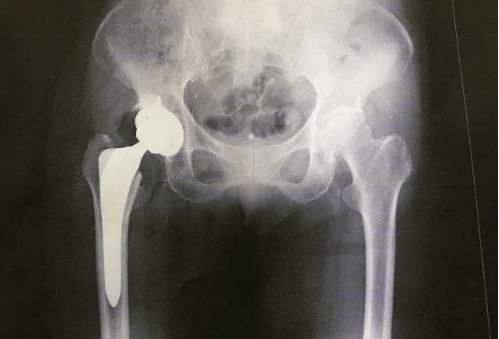

しかし、すでにインピンジメントにより変形性股関節症を発症している人もいるかもしれません。この場合、股関節インピンジメント手術は最良の選択肢ではなく、代わりに人工股関節置換術が必要になる可能性があります。

手術の目的は、股関節のボールとソケットの形状を復元し、完全な球形、ソケットが完全な円形のボウルになるようにすることです。